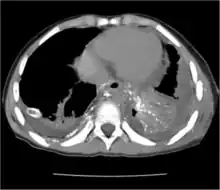

CT scan showing extensive chylothorax caused by leakage from the thoracic duct

Chest X-rays can detect a chylothorax. It appears as a dense, homogeneous area that obscures the costophrenic and cardiophrenic angles. Ultrasounds can also detect a chylothorax, which appears as an echoic region that is isodense with no septation or loculation. However, neither a normal chest x-ray nor an ultrasound can differentiate a chylothorax from any other type of pleural effusion.[1]